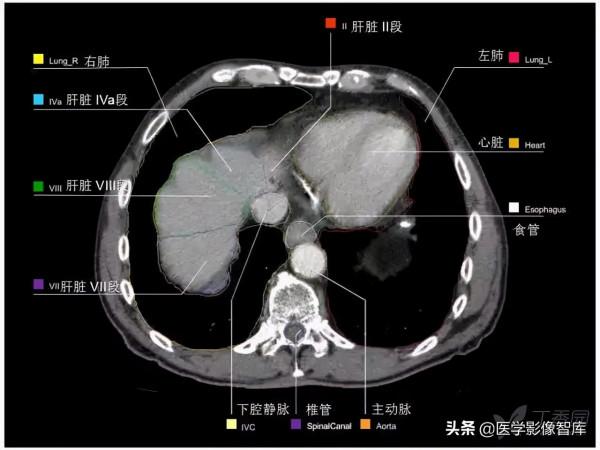

腹部CT